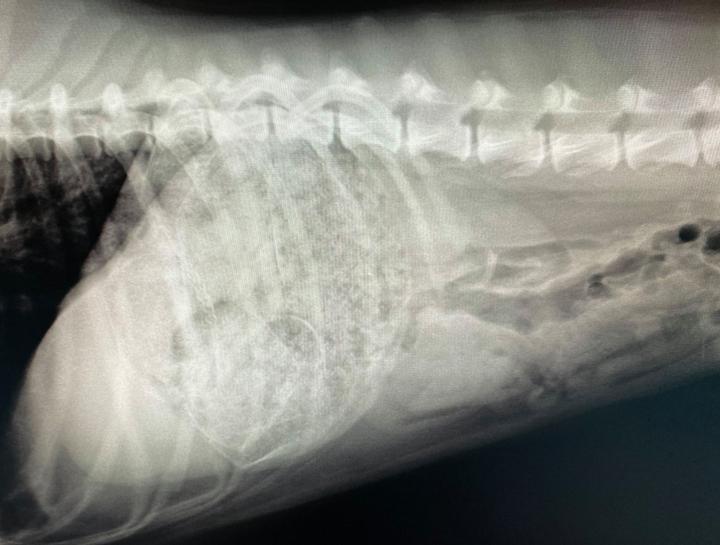

Pet Digital Radiology

Digital x-rays assist in diagnosing illness & injury.